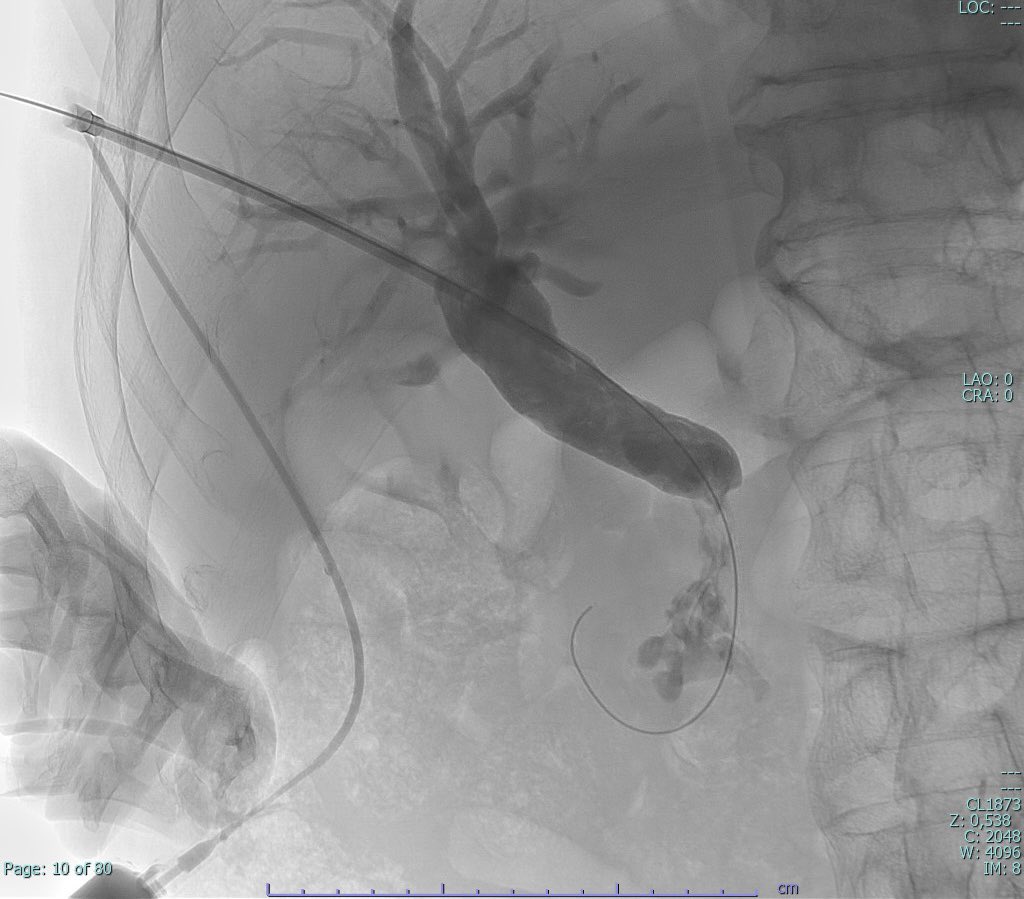

Manejo de vía biliar, colangioscopia percutanea, Rendez Vous, biopsia, stent cubierto, lo mejor para nuestros pacientes Hospital Temuco @aitt21 @teptips @rduranmendez @DiegoRad91 @dclemo81 @RadiologiaChile @sidi #ir @HHHATEMUCO @BostonSciLatam @colmedtemuco

Percutaneous - Endoscopic Rendez Vous for distal cholangiocarcinoma 1) Spyglass Biopsies 2) SEMS Partially Covered @intervencional @HHHATEMUCO @DouglasAdlerMD @BostonSciLatam